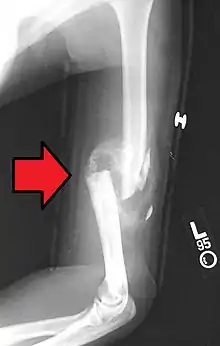

Вначале образуется соединительнотканная провизорная мозоль, к концу первой недели образуется остеоидная ткань, которая превращается либо непосредственно в костную, либо сначала в хрящевую, а затем в костную. Мозоль возникает из костеобразующих клеток надкостницы и эндоста. Образование костной мозоли играет важную роль в процессе срастания поврежденной кости. Костная мозоль, представляющая на рентгенограмме слегка затемненную область, в конце концов кальцифицируется и моделируется.

Костная мозоль перестраивается в нормальную кость примерно за один год.